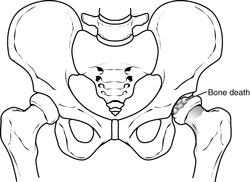

In the first stage of Perthes disease, the bone in the head of the femur slowly dies.